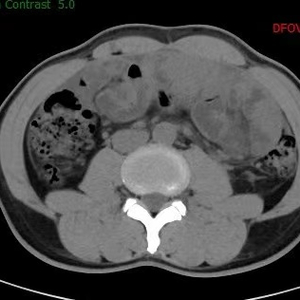

图说: 李先生入院腹部CT 采访对象供图(下同)

南院区普外科检查及会诊后发现,患者左下腹有一个25*20cm的硬质包块活动度差,有局限性压痛、反跳痛;CT检查显示小肠系膜纠集,周围线状包裹,提示“腹茧症可能,伴小肠不全梗阻”;患者肿瘤标志物、结核指标、自身免疫指标、胃肠镜等检验检查均为阴性。经讨论后,大家一致认为,造成李先生呕吐、腹痛、停止排便的“元凶”是腹茧症,患者小肠被纤维包膜层层包裹,失去蠕动的功能,因此演化为不完全性粘连性肠梗阻。手术剥离肠管外周增厚的纤维膜是解除梗阻、恢复正常进食的唯一途径。